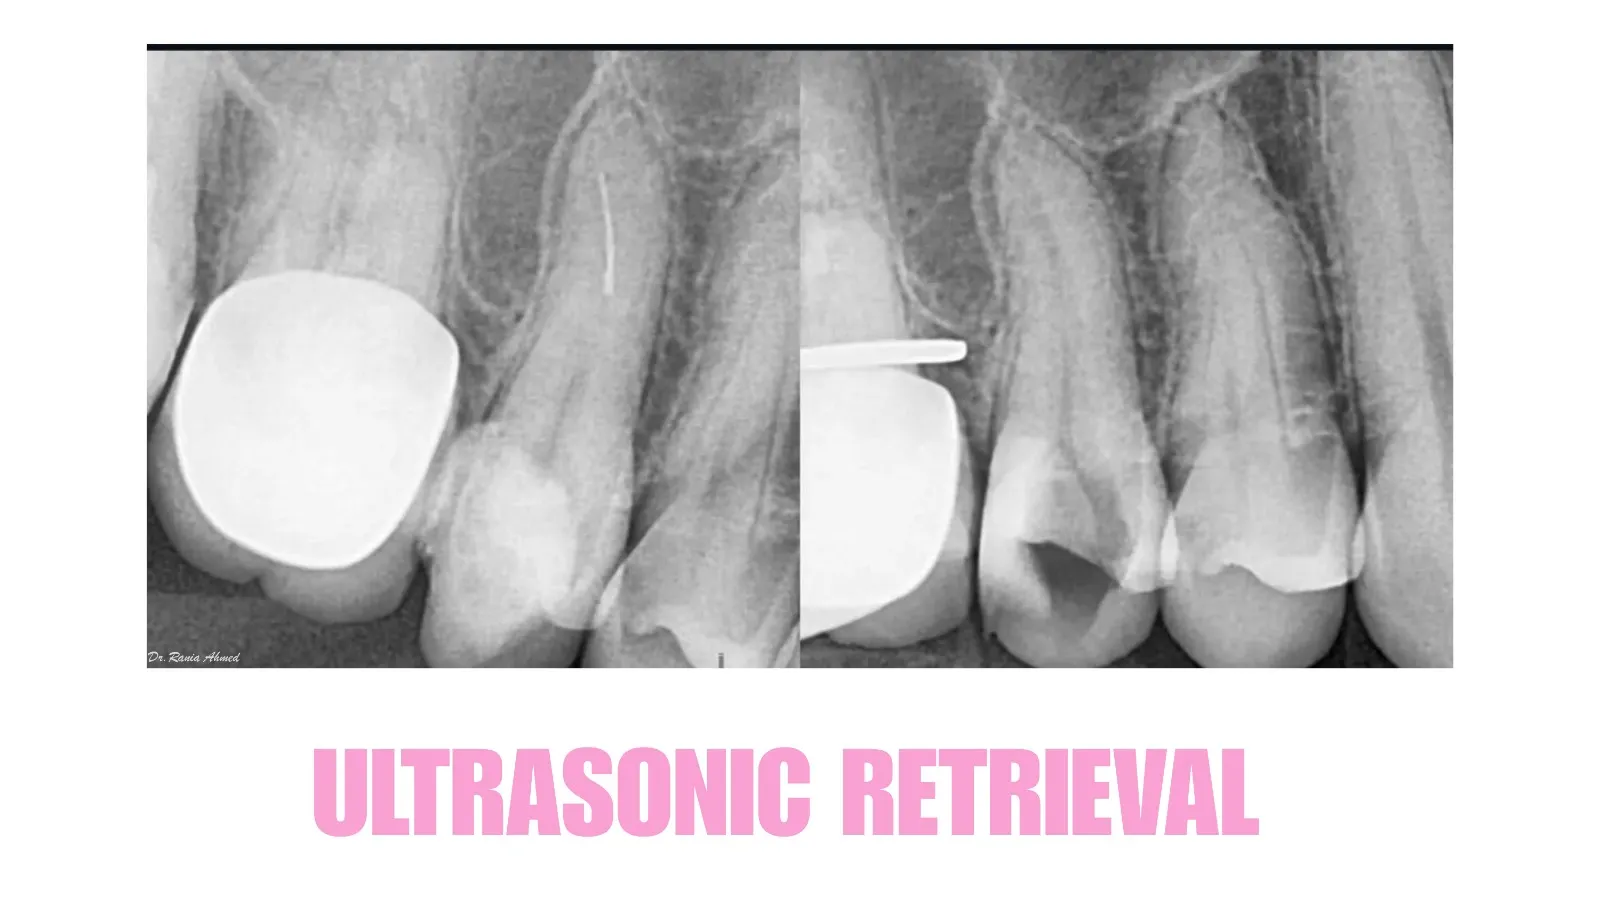

Endodontic Treatment